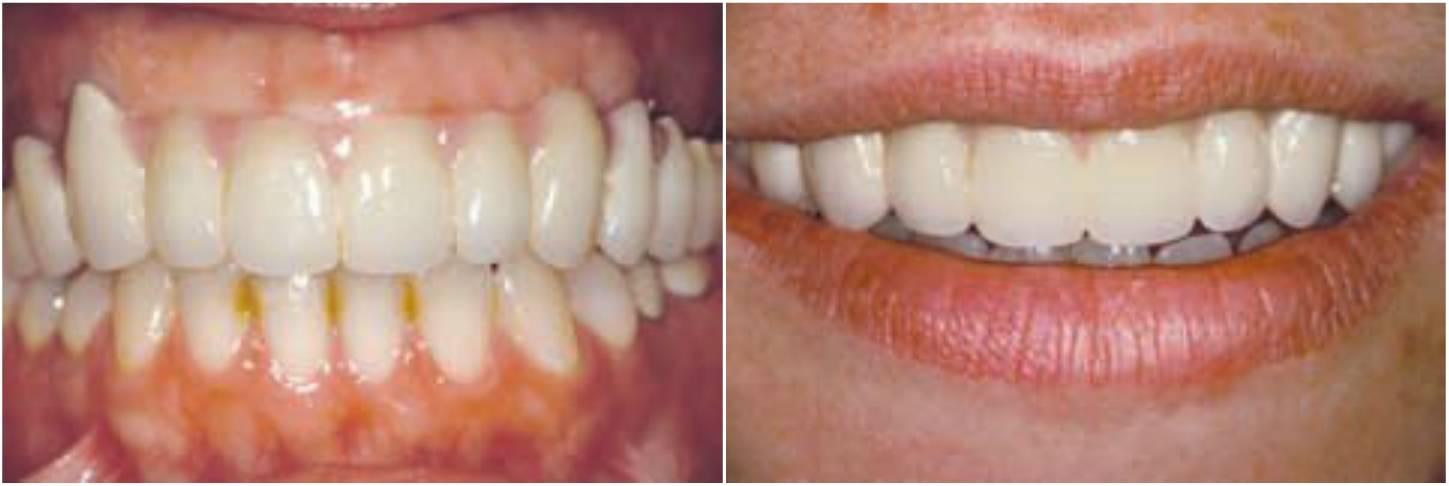

Básicamente existen dos enfoques para una prótesis PF-3: 1) una restauración híbrida compuesta por una dentadura con dientes con una subestructura acrílica y metálica o 2) una restauración de metal-porcelana (figs. 5-12 a 5-14; tabla 5-2).

Una alternativa a la prótesis tradicional fija de metal porcelana es la restauración híbrida (v. tabla 5-2). Este di seño utiliza una estructura metálica menor, con dientes artificiales y acrílico para unir estos elementos (fig. 5-15).

Esta restauración es menos cara de fabricar y es muy estética debido a los dientes artificiales prefabricados y al reemplazo de los tejidos blandos por el acrílico rosa. Además, el acrílico interpuesto entre los dientes y el armazón puede reducir fuerza de impacto de las cargas odusales dinámicas. La prótesis híbrida es más fácil de reparar ante una fractura, y el diente artificial puede sustituirse con un riesgo menor que el añadido de porcelana a una restauración tradicional ceramometálica. En cualquier caso, la fatiga del acrílico es mayor que en las prótesis tradicionales; de ahí que la reparación de la restauración se necesite con más frecuencia.

La determinación del espacio vertical de la corona de una restauración híbrida frente a una restauración tradicional de metal-porcelana es de 15 mm desde el hueso hasta el plano oclusal. Cuando la dimensión de la que se dispone es inferior a esta, se sugiere emplear una restauración de metal-porcelana. Cuando existe un espacio vertical de la corona mayor, se suele fabricar una restauración híbrida.